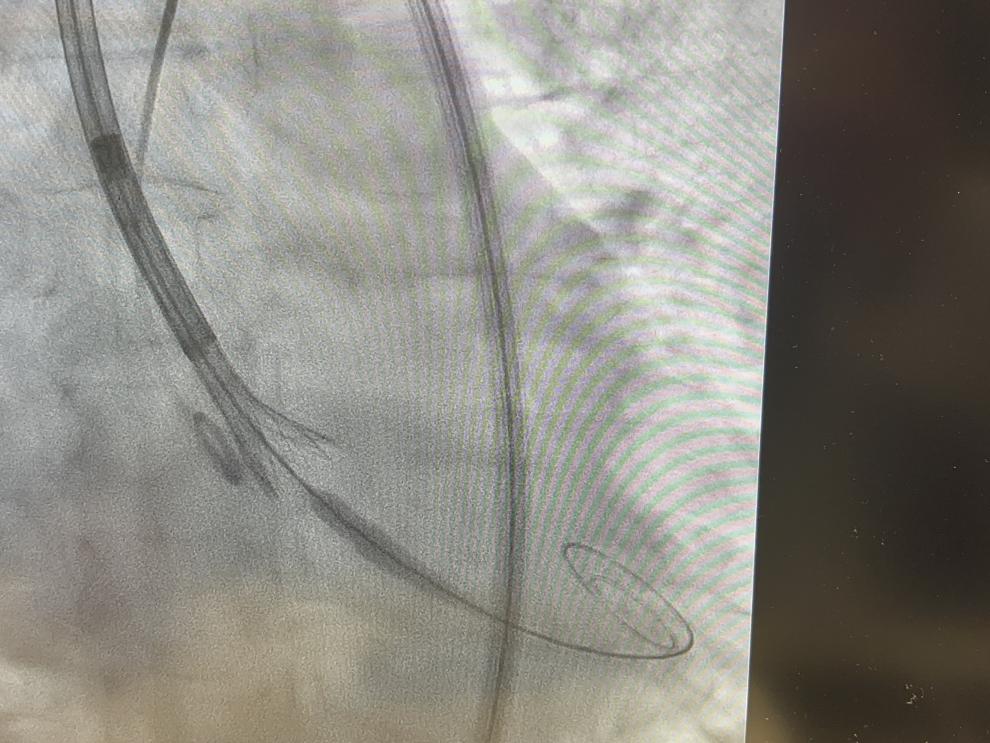

Imagen obtenida mediante rayos X durante una intervención cardiaca en la que se implanta un stent para mantener abierto un vaso sanguíneo.